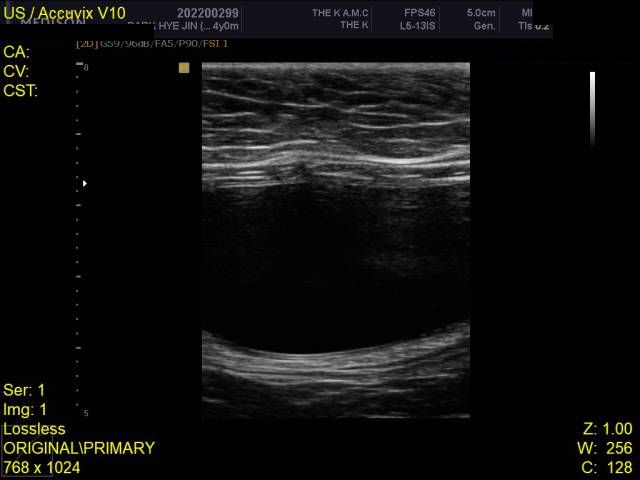

HCM의 진단의 golden standard 는 심장초음파 검사입니다. 하지만 첨부된 자료에는 심장 초음파 검사 결과가 없고

흉부 방사선 검사 또한 외측상이 결여되어 있어 자료로 판단할 수 없습니다.

주치의에게 요청하여 심장 초음파 검사를 진행해 보시기 바랍니다.